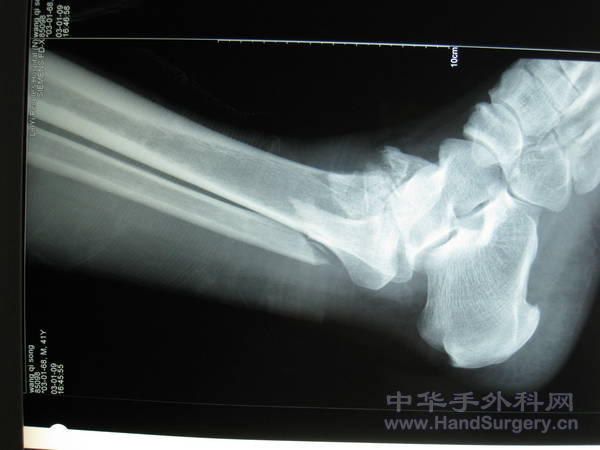

pilon骨折一例-手足外科魏宝富主任作品

这种骨折为从高坠落高能量致的损伤,损伤都较重,对重的有的主张一期行关节融合,如轻的可以行复位内固定,一般都要行植骨。

pilon骨折在哪做都是高难度手术,骨性支架的建立应该最重要,皮肤缺损对手足外科大夫来讲已经不是什么难题 ,希望看到踝关节关节面的x线或ct。

魏主任:你的手术做的很好,但是不知关节面是如何处理的,植骨了吗?是急症做的还是消肿以后做的?切口愈合如何?还有外侧的关节面好像没有处理?

对于此类骨折,手术最关键所在应该是先恢复腓骨解剖位置,其余骨折块做起来较容易些。另外需要注意植骨支撑,再者注意下胫腓关系一定要稳定!不要轻易去做融合!个人理解